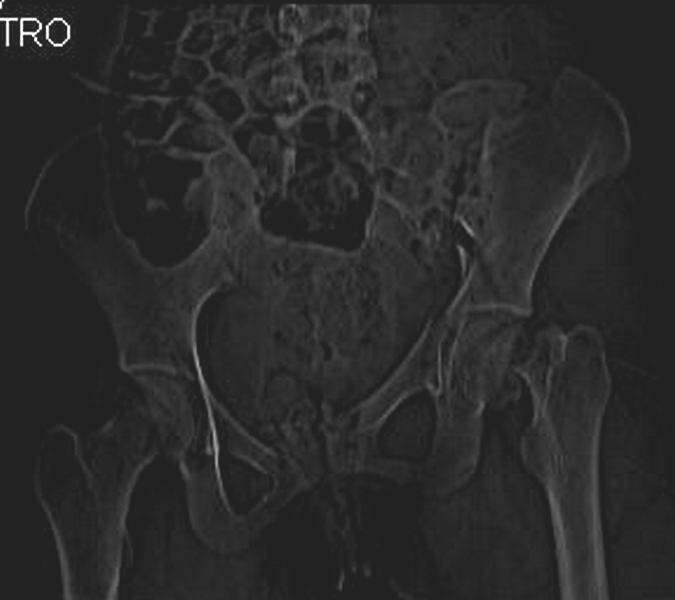

Механизм травмы падение с 5 этажа. Краткий диагноз:закрытый перелом левой ключицы, левого плеча, закрытый вертикально и ротационно нестабильный перелом костей таза:закрытый перелом левой подвздошной кости, переломы лонной кости справа, перелом обоих колонн вертлужной впадины слева;субкапитальный перелом шейки левой бедренной кости со смещением.

По тактике лечения таза возникли следующие вопросы:

1. С чего начать - фиксации переломов вертлужной впадины или устранения деформаций таза?

2. Надо ли фиксировать шейку или фиксировать бедро в аппарате вместе с тазом, а после сращения таза планировать ТЭП ТБС?